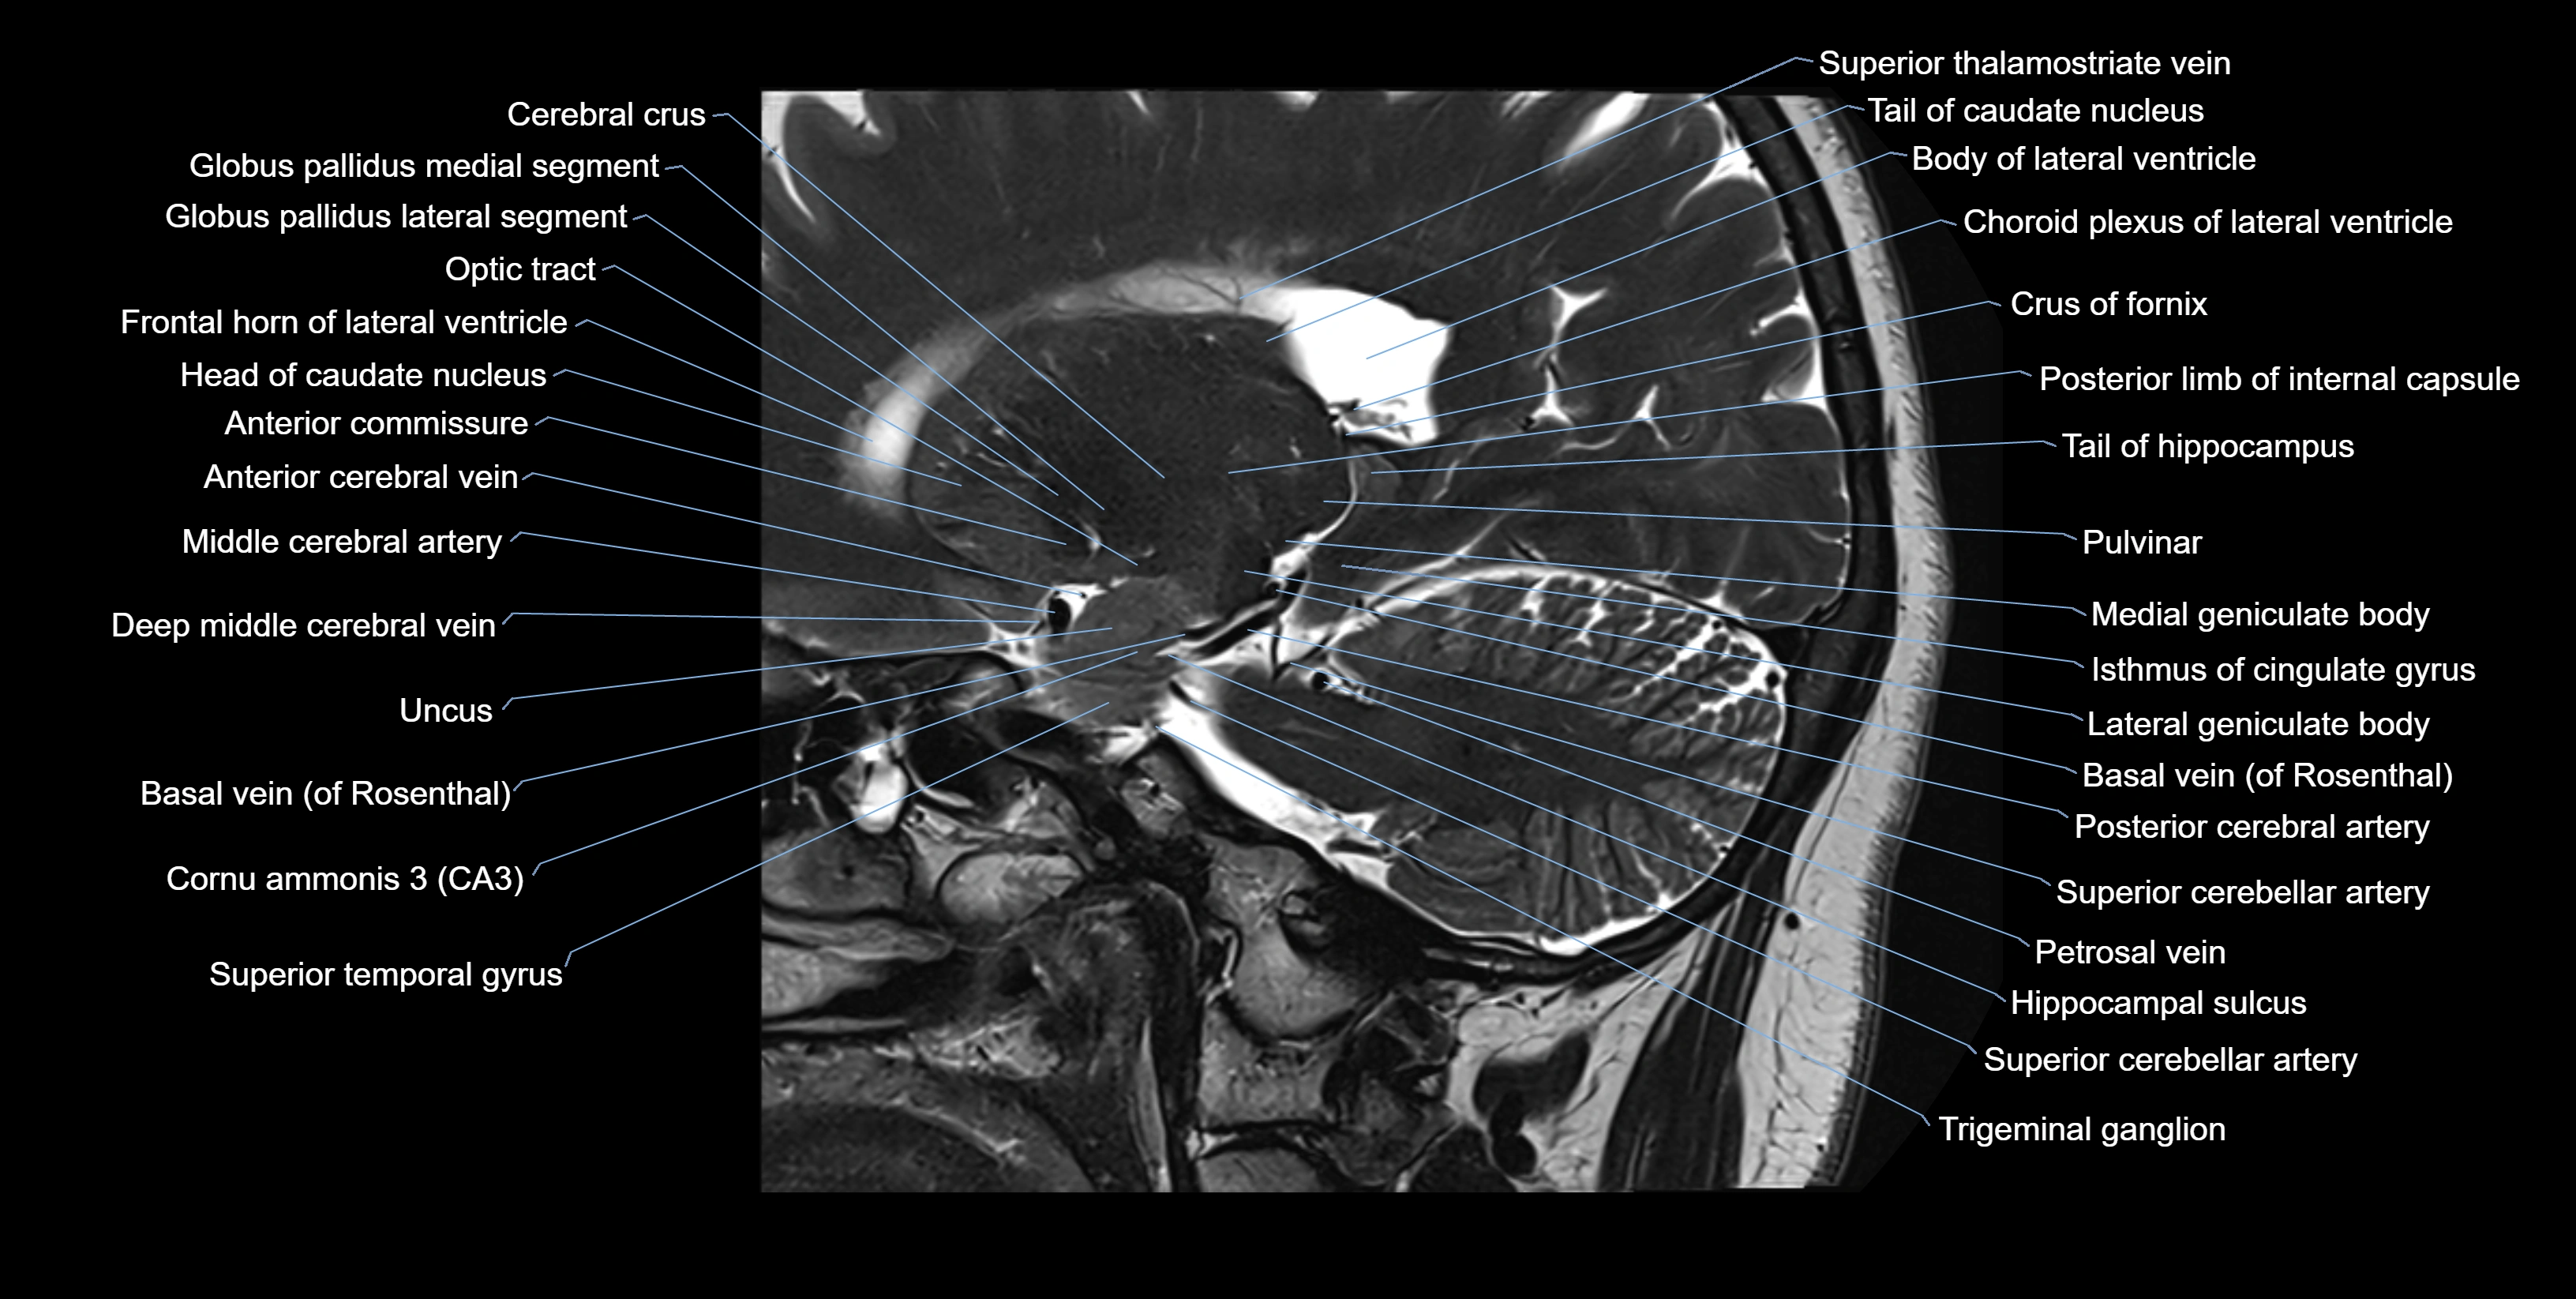

MRI images

image